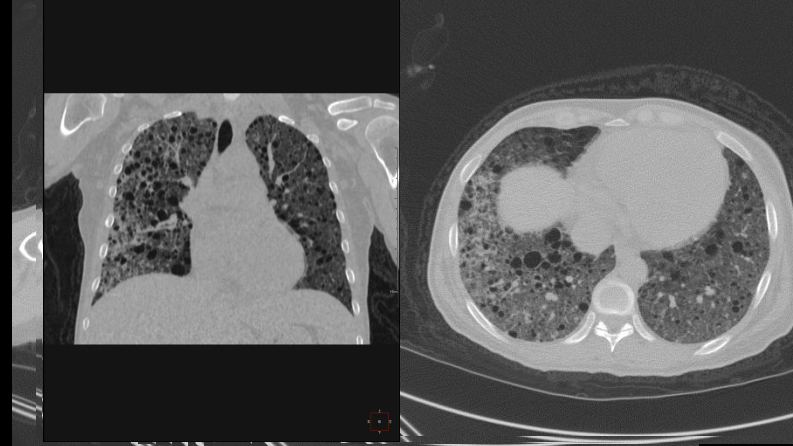

肺淋巴管肌瘤病合并双侧巨大肾血管平滑肌脂肪瘤(X线、CT、MR).pdf